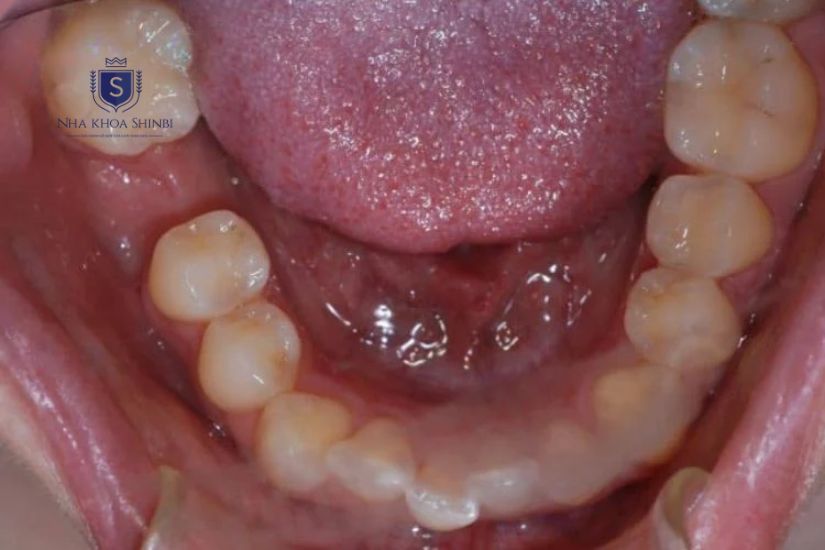

Răng cấm sau khi cắt chỉ